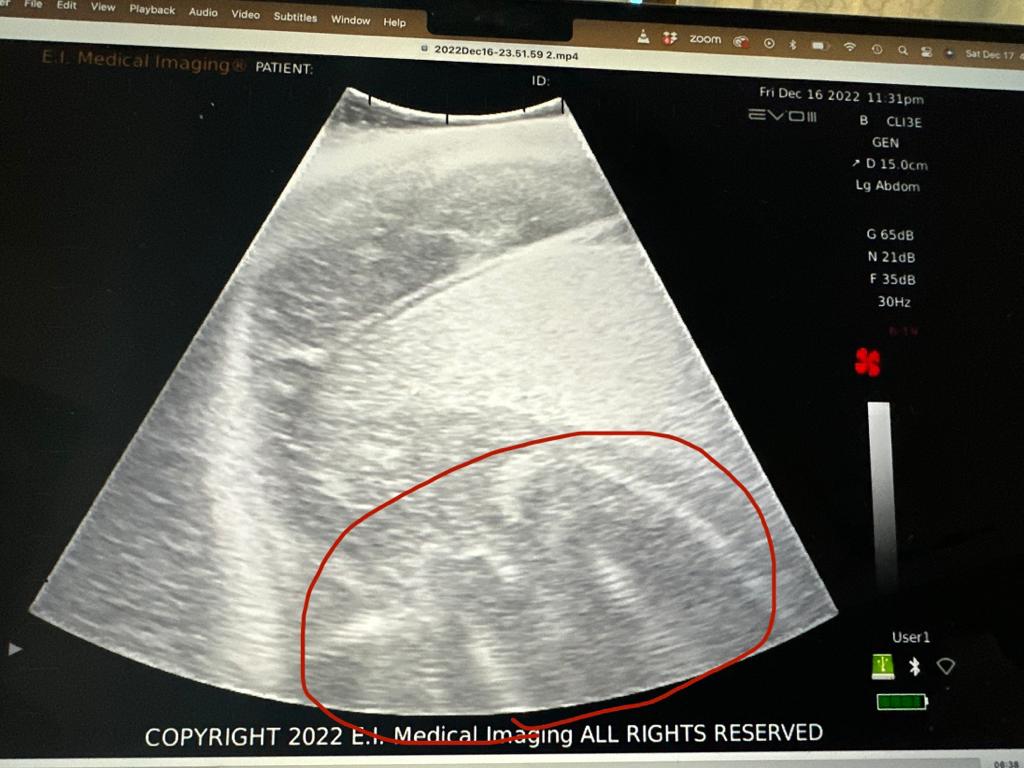

The study’s uniqueness lies in its innovative use of a fully submersible ultrasound developed by EI Medical. Scientists ventured into the depths to examine free-swimming female bull sharks. In a remarkable twist, they confirmed the presence of embryos in three female sharks, unveiling the hidden marvels of underwater maternity.

Equally remarkable is the technological leap this study represents. The successful development and use of a new, non-invasive underwater HD ultrasound technology affectionately called the “Aquanaut,” opens new avenues for studying marine life in their natural habitats without disruption.